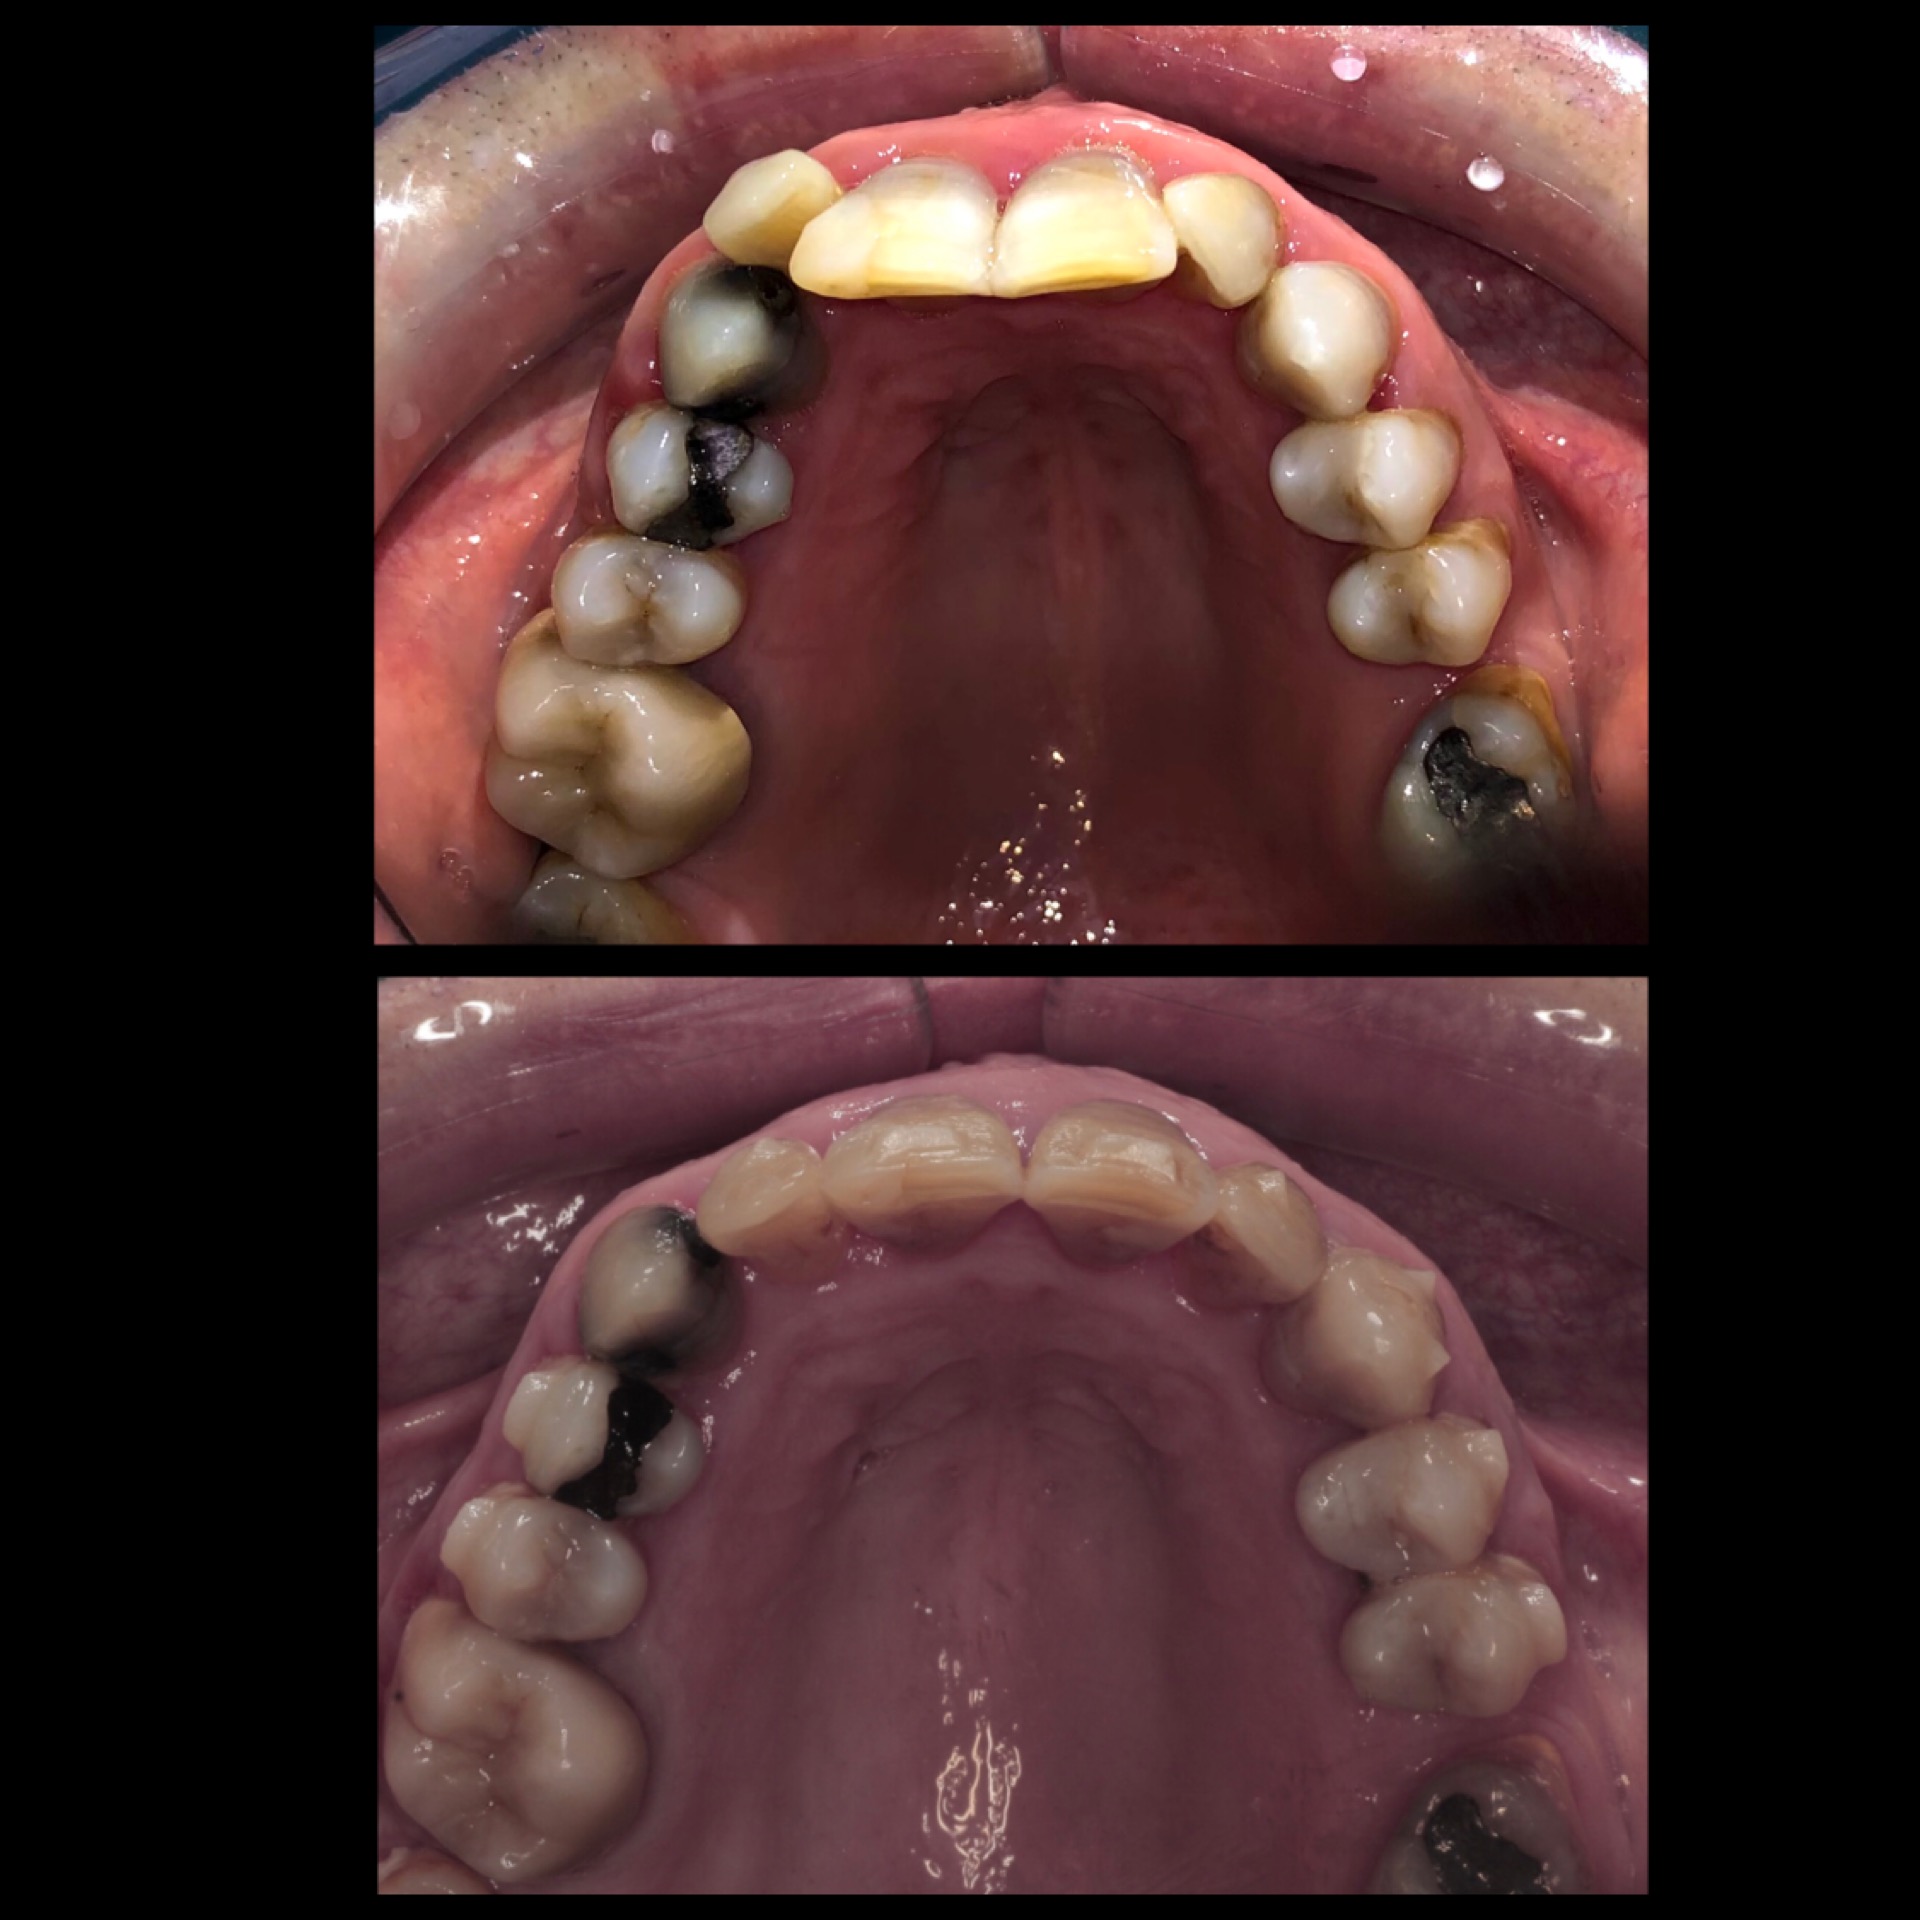

• Impronta con scanner 3d , foto iniziali intra ed extraorali per la pianificazione del caso.

• Elaborazione del ClinCheck da parte dell’ortodontista in cui verranno programmati tutti i movimenti dei singoli denti.

• Simulazione 3D del  trattamento in cui il paziente potrà vedere il risultato finale.